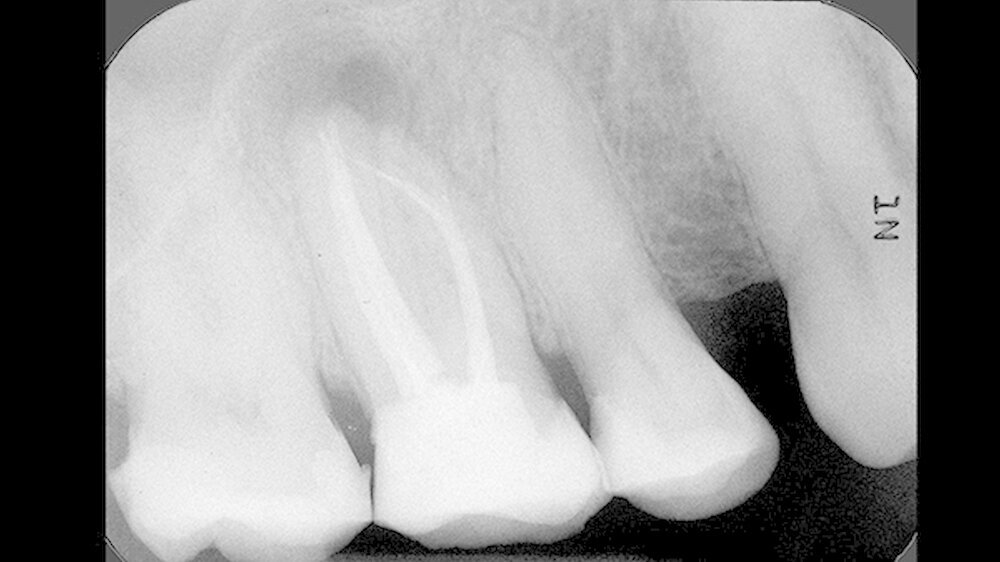

Er berichtete, dass an diesem Zahn ungefähr ein Jahr zuvor eine Wurzelkanalbehandlung alio loco durchgeführt worden war. Das angefertigte Röntgenbild (Abbildung 1) zeigte eine apikale Aufhellung und ein frakturiertes Wurzelkanalinstrument, das vermutlich über den Apex des mesiobukkalen Wurzelkanals herausragte. Die Füllung aller vier Wurzelkanäle erschien röntgendicht, wandständig und ohne Zeichen von Porositäten oder Lufteinschlüssen.